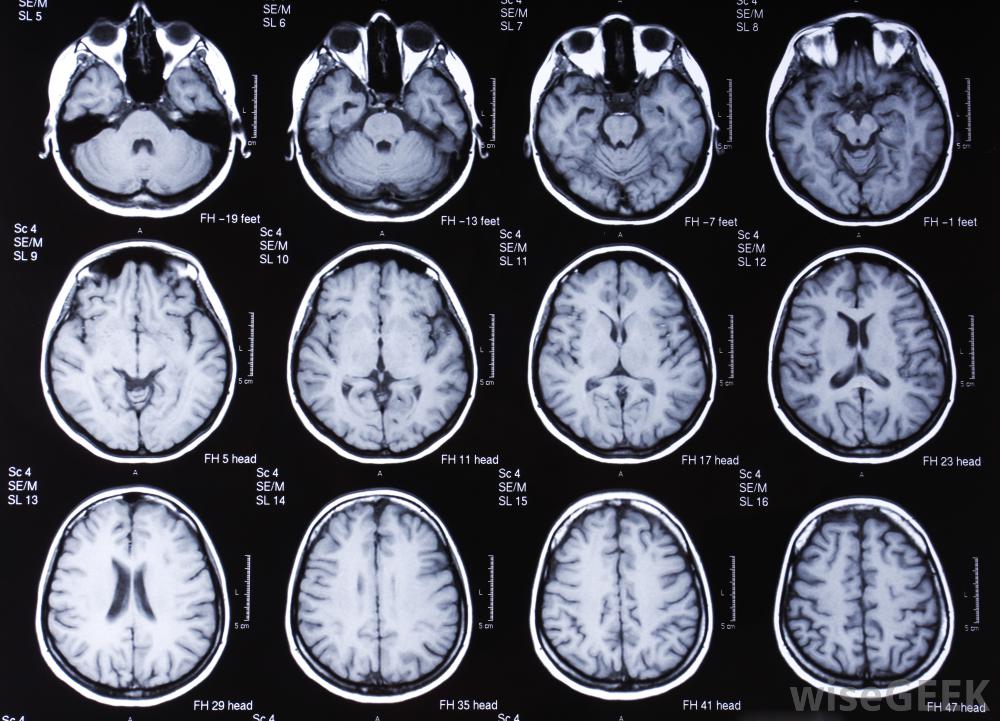

脑部核磁共振扫描可帮助确定脑震荡的严重程度。